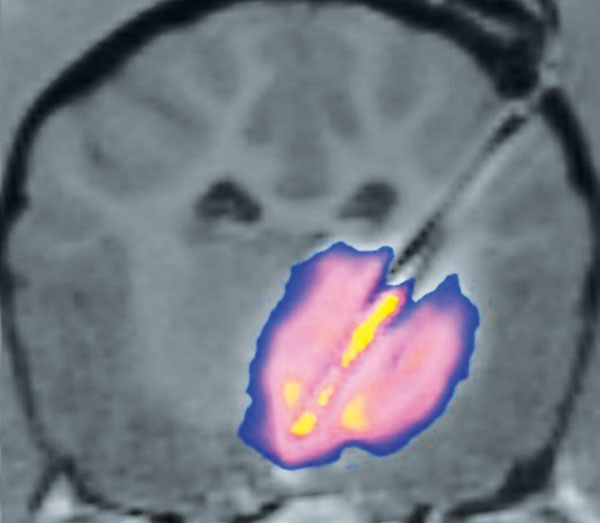

Figure 3 — 1 cm OmniArray™ PBIC delivery of MRI contrast agent in canine parenchymal brain tissue at 8 ul/min infusion rate.